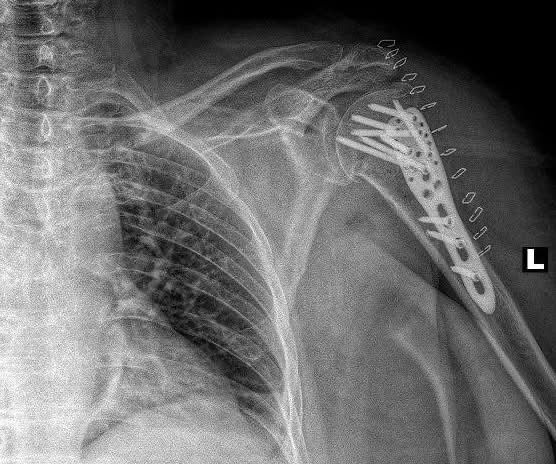

The funds will be used to procure mechanical fixation systems and implants essential for bone reconstruction and stabilization, including osteosynthesis implant kits, spinal stabilization systems, joint endoprostheses, and other surgical materials. SVOYI will handle the direct purchase and distribution of these components to hospitals treating wounded patients across Ukraine.

The primary treatment for severe bone damage is osteosynthesis—a procedure involving precise repositioning and fixation of bone fragments using mechanical implants. This approach is crucial to preserving limb functionality and enabling recovery for patients.